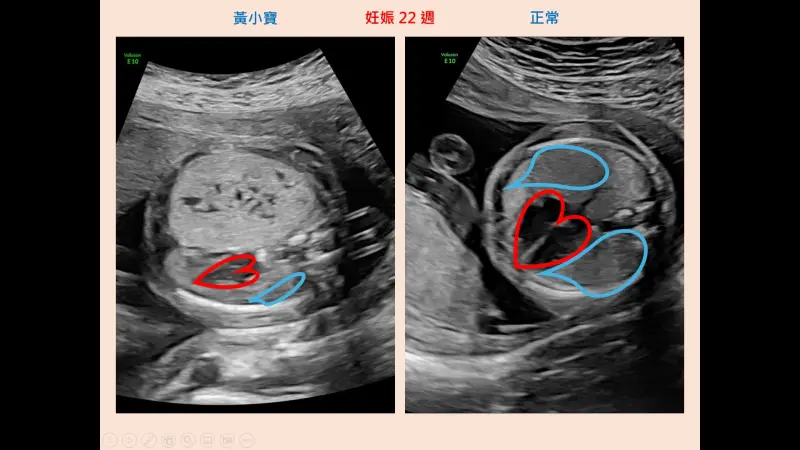

葉長青指出,黃媽媽在懷孕22週時,因為產檢超音波發現胎兒肺部腫瘤,由宜蘭轉診至台北榮總,經高層次超音波檢查,證實胎兒右側肺部有大型CPAM,並已將心臟與縱膈腔推向側邊,但其他器官結構正常,經會診兒童外科後,黃媽媽和家人決定繼續懷孕。